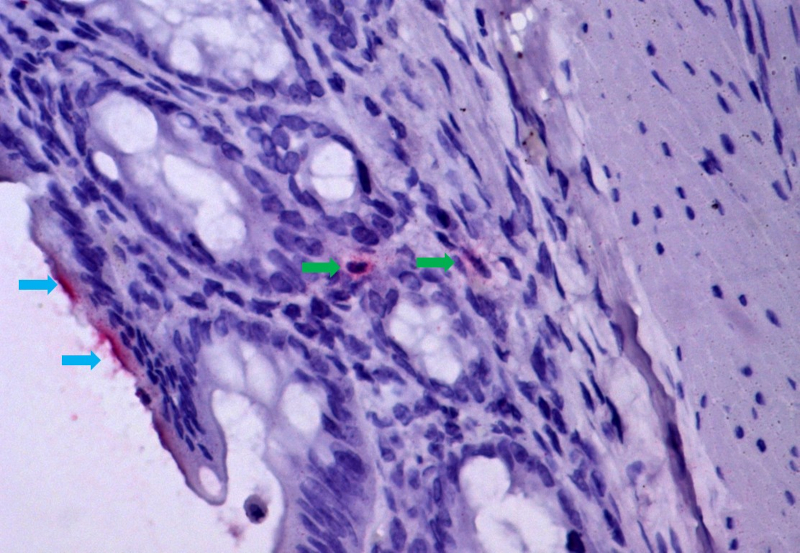

El virus de la COVID-19 manipula el ARN de la célula huésped para desactivar el sistema inmunitario

Un estudio de la Universidad Federal de São Paulo describe cómo el SARS-CoV-2 interactúa de manera inédita con el ARN de las células pulmonares infectadas; los resultados pueden orientar la búsqueda de nuevos tratamientos y vacunas